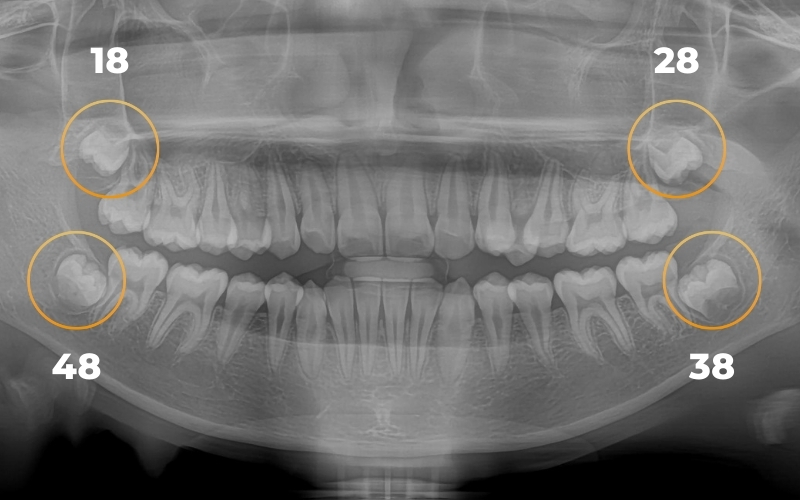

Bước 1. Thăm khám và chuẩn bị

Khám tổng quát: Bác sĩ kiểm tra răng miệng và đánh giá tình trạng răng khôn.

Chụp X-quang: Xác định vị trí, hướng mọc (lệch, ngầm), chân răng và cấu trúc xương.